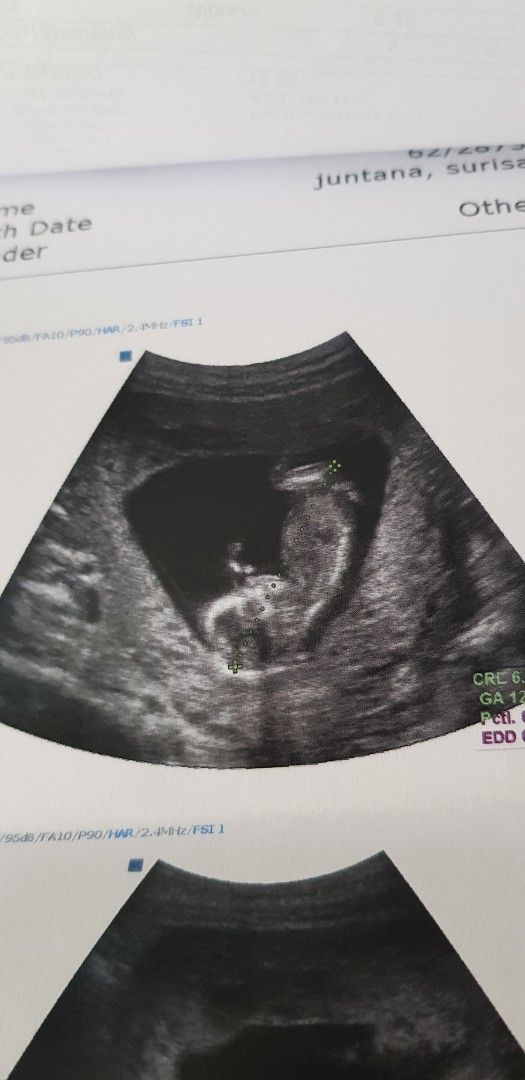

11+3จ้า